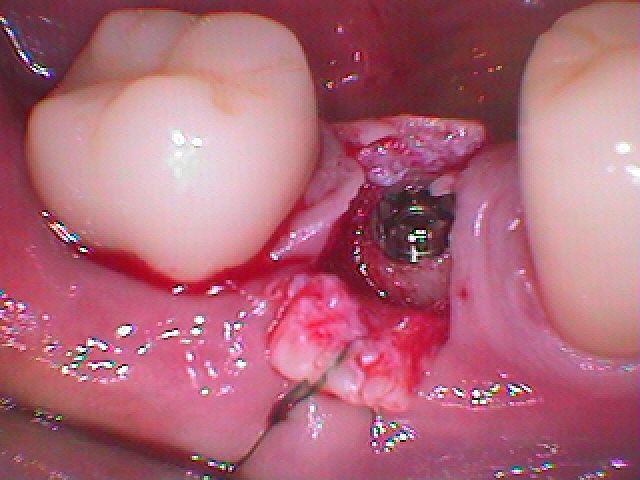

しっかりと骨内にインプラントが入りました

頬側に舌側の角化歯肉をもっていっています